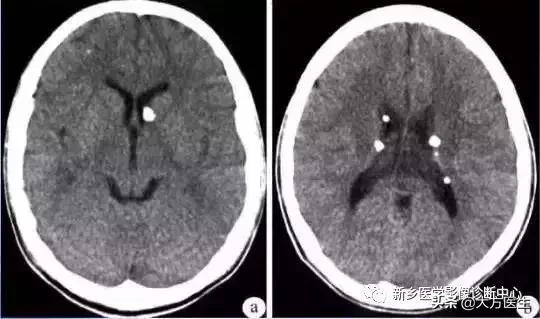

1、少突胶质细胞瘤

多见于青少年,类圆形肿块,边界清楚,密度不均,点片状、弯曲条带状、不规则或皮层脑回状钙化,可能轻度水肿,轻度强化。

MR:为长T1长T2信号,钙化均为低信号。